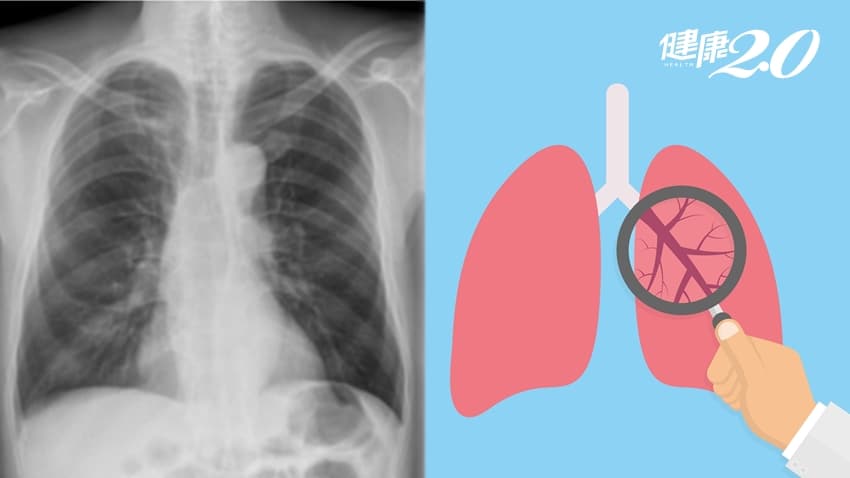

醫師建議他隔年要用電腦斷層進行追蹤,但他仍選擇安排胸部X光檢查,結果無異常;直到去年底,他做了肺部電腦斷層檢查,這才發現原本局部纖維化的右上肺葉,已長出一顆1.5公分的腫瘤。

▲ 患者X光影像未顯示肺癌(左圖);肺部電腦斷層影像中,肺癌清晰可見(右圖)。

很多人以為「定期胸部X光檢查就能發現早期肺癌」,澄清醫院柏忕健康管理中心醫學影像科醫師洪盈盈澄清,這是錯誤的觀念;事實上,1公分以下的肺部腫瘤很難發現,甚至是1.5公分的腫瘤也不一定能看得到。

洪盈盈說明,因為很多肺癌早期生長時密度很低,呈現出來的毛玻璃影像看起來淡淡的,也有可能藏在胸椎、心臟、肋骨、橫膈膜或肝臟前後方,這些都是X光檢查的死角。

電腦斷層敏感度比X光高

低劑量肺部電腦斷層(LDCT)是目前醫界公認可以早期發現肺癌的篩檢工具;單次輻射暴露量較低,且檢查時間短,可在一次憋氣內(10-15秒)完成全肺臟的掃描,也突破過去胸部X光篩檢敏感度不足的限制。